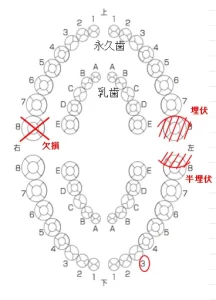

歯式(歯並びの様子を表した記号・図)ごとに乳歯から永久歯への生えかわりの一般的な年齢は以下の図の通りです。

ただし、これはあくまでも平均であり個人差があります。

乳歯全体の交換が平均から大きく外れていないか、定期的に検診で調べることが重要です。

また、今回のお子さまの症例のように口腔内で1本だけ明らかに生えてこない歯があるなどといったことにも注意が必要です。